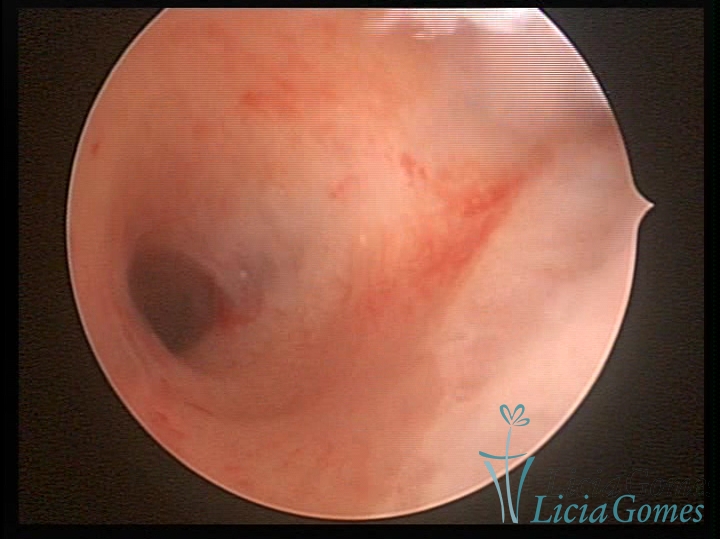

Unicornuate uterus

It presents a tubular cavity with an impaired intracavitary space, resembling the shape of a banana, whose the narrowest edge contains the tubal ostium. The endometrium is compatible with the menstrual cycle and the cervical canal is normal, in structure and trophism.